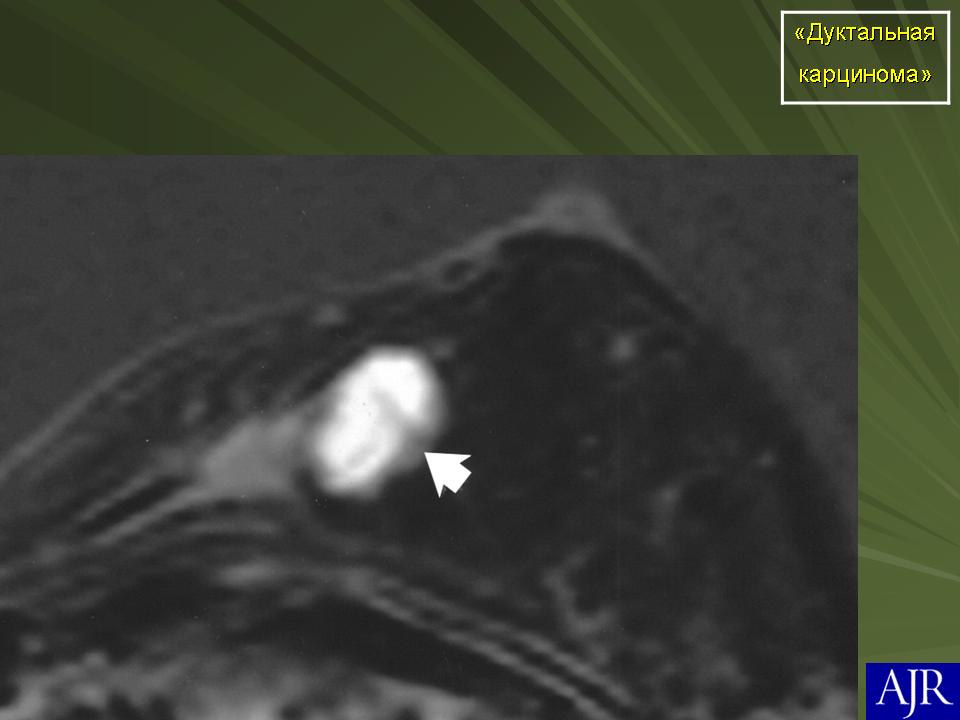

Протоковая карцинома

Рак молочной железы

Инвазивная (или инфильтрирующая) протоковая карцинома – это наиболее часто встречающаяся форма рака молочной железы. Она составляет около 80 % из всех форм. В отличие от протоковой карциномы in situ, инвазивная карцинома характеризуется тем, что раковый процесс уже вышел за пределы молочного протока и распространяется на нормальные ткани молочной железы. Характерной особенностью инвазивной протоковой карциномы является очень твёрдая припухлость с неровными краями, которая спаяна с окружающим тканям. Сосок молочной железы или кожа вокруг него может быть втянута.

Часто на маммограммах в области опухоли выявляются микрокальцинаты, что связано с том, что в опухоли происходит омертвление ее клеток (некроз), которые в последствие пропитываются солями кальция. Опухоль при инвазивной карциноме может быть различных размеров, и у клеток может быть различное время деления, так что некоторые клетки растут быстрее других.